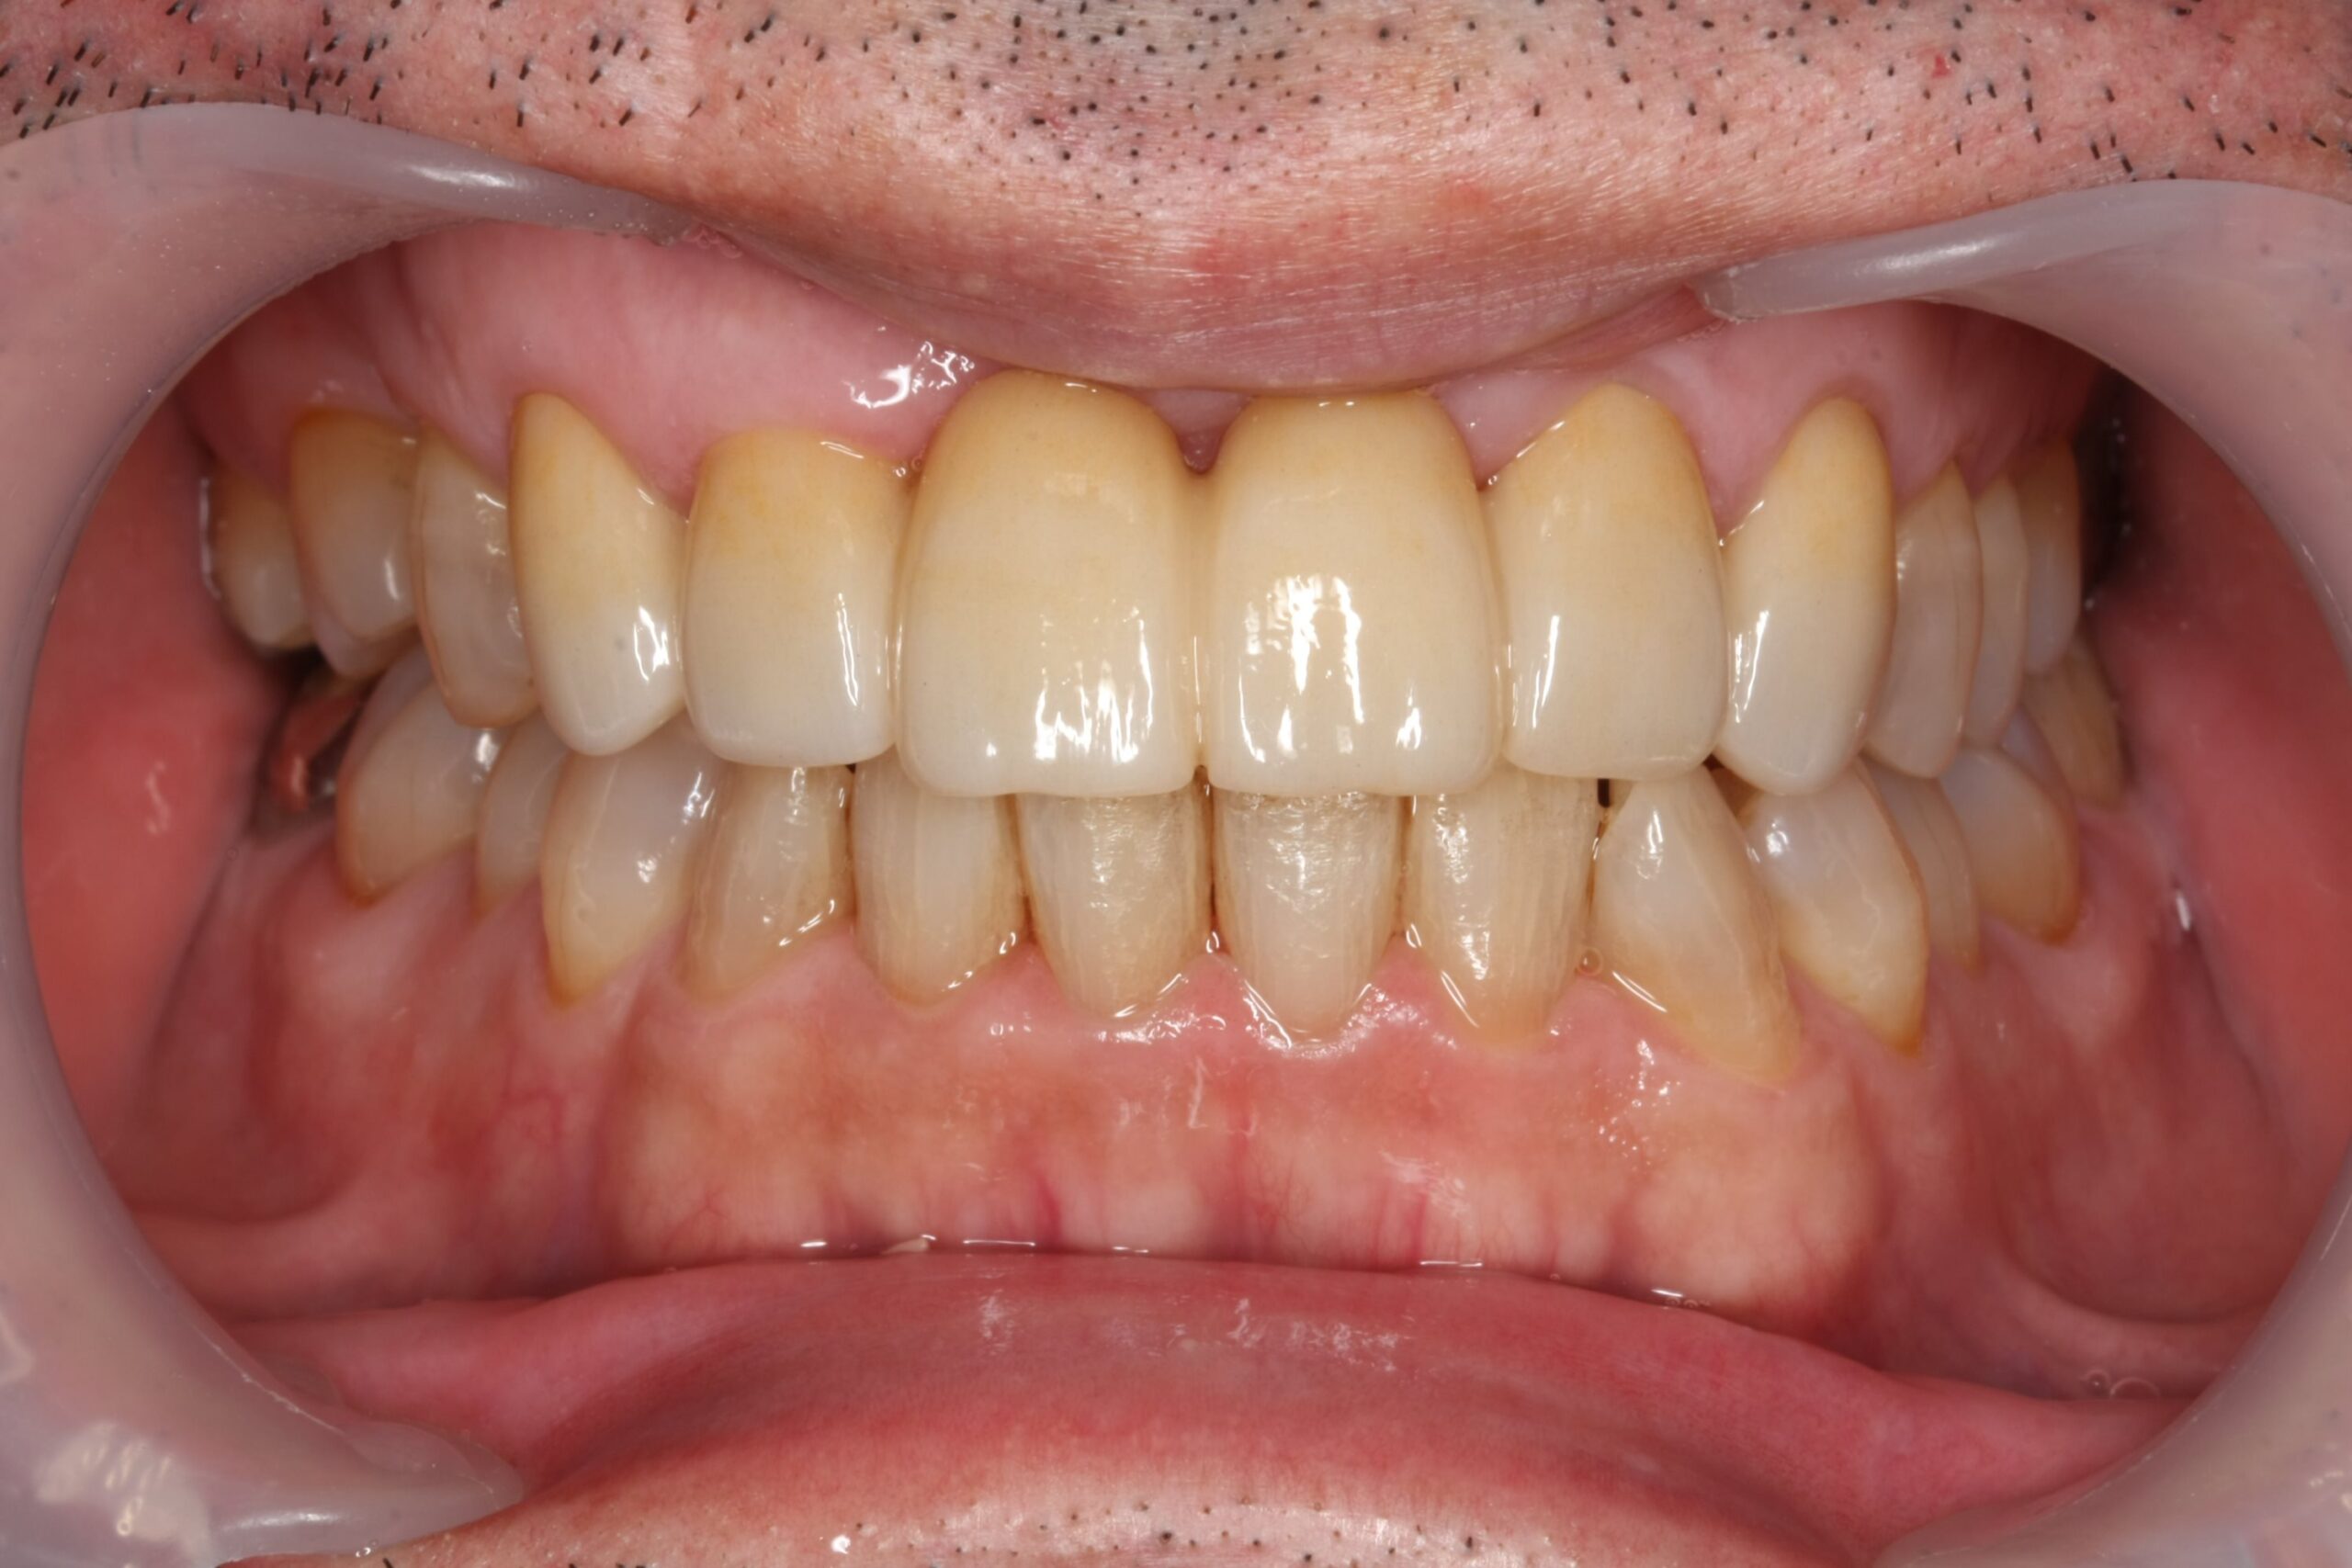

装着後1年半経過

装着後1年半が経過した状態です。

大きなトラブルなく使用できており、今後も定期的に噛み合わせや清掃状態を確認していきます。

この症例では、前歯の根の先に大きな病変があり、保存が難しい状態でした。

インプラント治療も選択肢の一つでしたが、骨の状態から難易度が高くなる可能性があったため、患者様と相談し、今回はジルコニアブリッジで治療する方針としました。

抜歯後すぐに最終的なブリッジを作るのではなく、歯ぐきや骨の治癒を待ってから、最終的な被せ物を作製しています。

そのため治療期間は長くなりましたが、形態や清掃性、噛み合わせを確認しながら進めることができました。

前歯の治療では、見た目だけでなく、歯ぐきの形、噛み合わせ、清掃のしやすさも大切です。